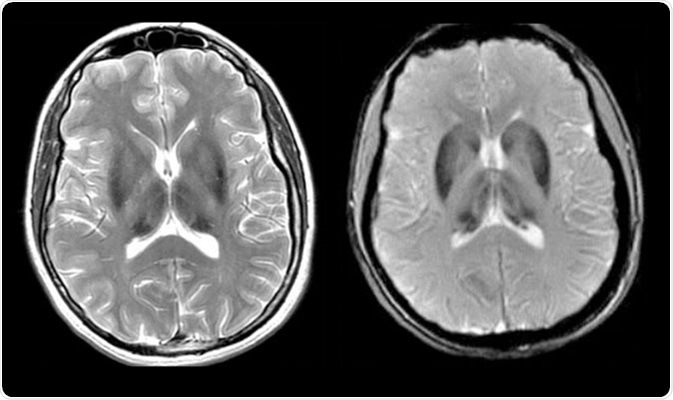

Aceruloplasminemia - Axial T2-weighted and axial GRE image demonstrates homogeneous iron deposition in caudate, putamen, globus pallidus and thalamus

Aceruloplasminemia - Axial T2-weighted and axial GRE image demonstrates homogeneous iron deposition in caudate, putamen, globus pallidus and thalamus. Image Credit: UNIFESP

The disease is further confirmed by magnetic resonance imaging (MRI) studies. The MRI is mainly used to generate cross-sectional images of different organs, especially brain and liver, to detect iron accumulation. In addition, genetic tests are done to identify and analyze the causative mutations in CP gene.